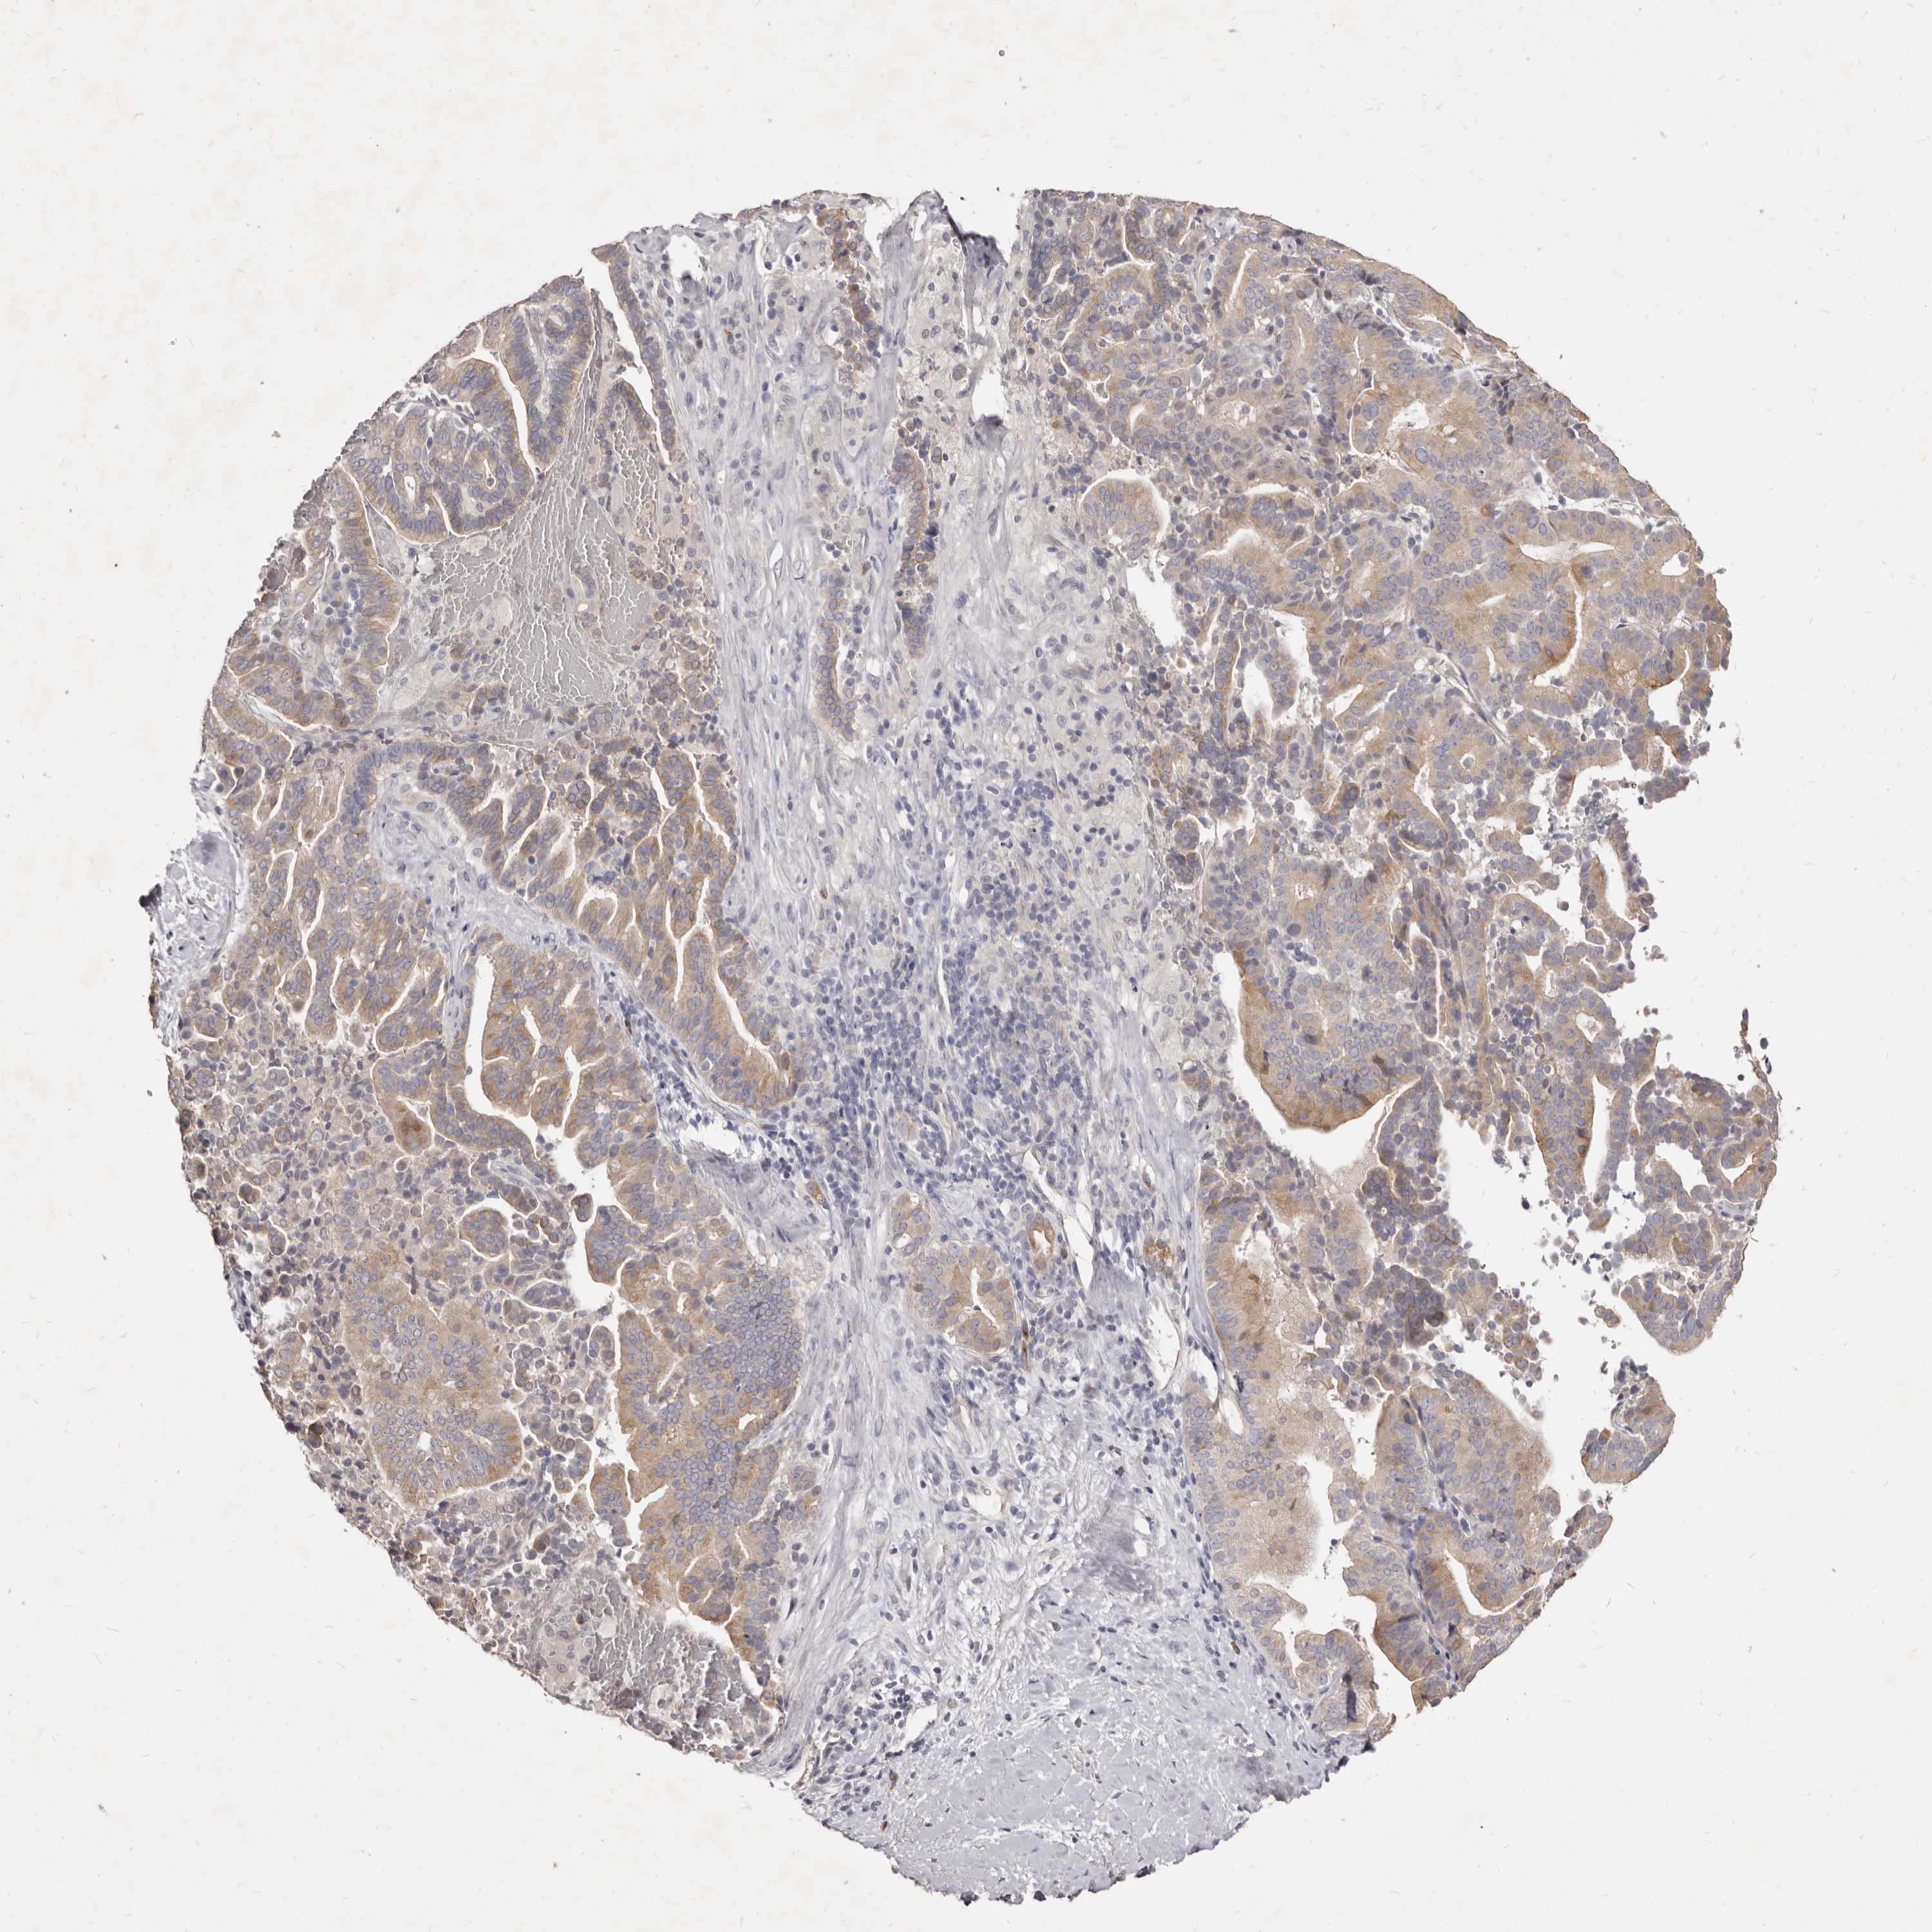

LIVER CANCER - Protein expressioni

A mouse-over function shows sample information and annotation data. Click on an image to view it in a full screen mode. Samples can be filtered based on level of antibody staining by selecting one or several of the following categories: high, medium, low and not detected. The assay and annotation is described here.

Note that samples used for immunohistochemistry by the Human Protein Atlas do not correspond to samples in the TCGA dataset.

Antibody stainingi

Antibody staining in the annotated cell types in the current human tissue is reported as not detected, low, medium, or high, based on conventional immunohistochemistry profiling in selected tissues. This score is based on the combination of the staining intensity and fraction of stained cells.

Each image is clickable and will lead to virtual microscopy that enables deeper exploration of all samples and also displays staining intensity scores, fraction scores and subcellular localization as well as patient and tissue information for each sample.

Antibody HPA023081

Antibody HPA023103

Antibody HPA024795

Staining

High

Medium

Low

Not detected

Intensity

Strong

Moderate

Weak

Negative

Quantity

>75%

75%-25%

<25%

None

Location

Nuclear

Cytoplasmic/membranous

Cytoplasmic/membranous,nuclear

Cholangiocarcinoma

Carcinoma, Hepatocellular, NOS